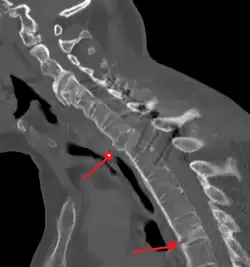

The earliest changes demonstrable by plain X-ray shows erosions and sclerosis in sacroiliac joints. Progression of the erosions leads to widening of the joint space and bony sclerosis. X-ray spine can reveal squaring of vertebrae with bony spur formation called syndesmophyte. This causes the bamboo spine appearance. A drawback of X-ray diagnosis is the signs and symptoms of AS have usually been established as long as 7–10 years prior to X-ray-evident changes occurring on a plain film X-ray, which means a delay of as long as 10 years before adequate therapies can be introduced.[25]

-

Lateral X-ray of the mid back in ankylosing spondylitis -

Lateral X-ray of the neck in ankylosing spondylitis -

CT scan showing bamboo spine in ankylosing spondylitis -